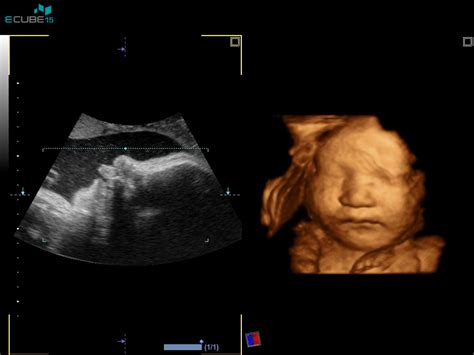

Prezgodnji porod je definiran kot porod, ki se zgodi pred 37. tednom nosečnosti, kar predstavlja približno 6 % vseh porodov. Porod v 32. tednu spada v kategorijo zelo zgodnjega poroda (od 24. do 32. tedna). V 32. tednu nosečnosti se otrok še vedno zdi nekje v prihodnosti, vendar se tako nosečnica kot dojenček pripravljata na številne načine. Otrok se je najverjetneje že obrnil z glavo navzdol, pripravljen na potovanje skozi porodnega kanala. V tem tednu je otrok velik kot listnati ohrovt, meri približno 42 centimetrov od glave do pet in tehta okoli 2150 gramov. V zadnjih 8 tednih do poroda bo dojenček pridobil od 1,5 do 2 kilograma.

Nosečniški trebušček v 32. tednu meri približno 30 do 34 centimetrov od vrha maternice do medenične kosti. V obdobju med 32. in 34. tednom nosečnosti se dojenček običajno "spusti" od reber navzdol v medenico, kjer ostane z glavo navzdol do poroda. Ko se to zgodi, nosečnica opazi, da trebušček nosi nižje.